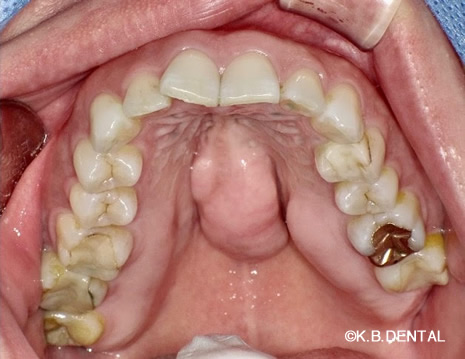

口蓋隆起 症例5(口蓋隆起形成術)

無痛治療での口蓋隆起形成術。骨ノミとピエゾサージェリーを使い、低侵襲な手術を行いました。上顎の違和感がなくなります。

料金

静脈内鎮静法による麻酔代込み:約15万円(保険適用外)

口蓋隆起 症例6(口蓋隆起形成術+親知らず抜歯)

無痛治療で口蓋隆起形成術。同時に左上の親知らずも抜歯しました。ピエゾサージェリーも使い低侵襲な手術を行いました。上顎の違和感がなくなります。